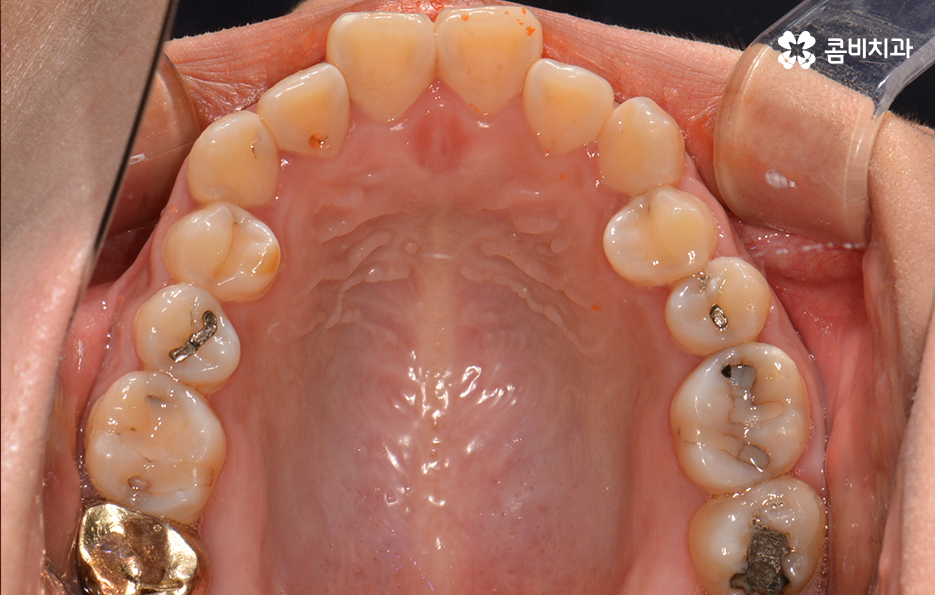

교정이 시작되기 전에 충치가 있다면 미리 치료 후 진행합니다.

(좌) 얼굴을 고려하여 돌출입을 개선하는 치료 계획을 세움, (우) 사랑니 발치와 상악 14,24 / 하악 34,44 치아 발치 진행

심한 돌출입은 아니었기 때문에 비수술적인 방법으로 치료 진행